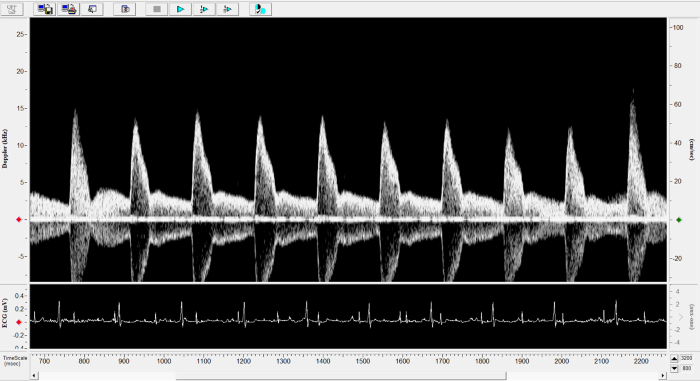

Rat - Transverse Aorta

Rat - Transverse Aorta. Image Credit: Scintica Instrumentation Inc.